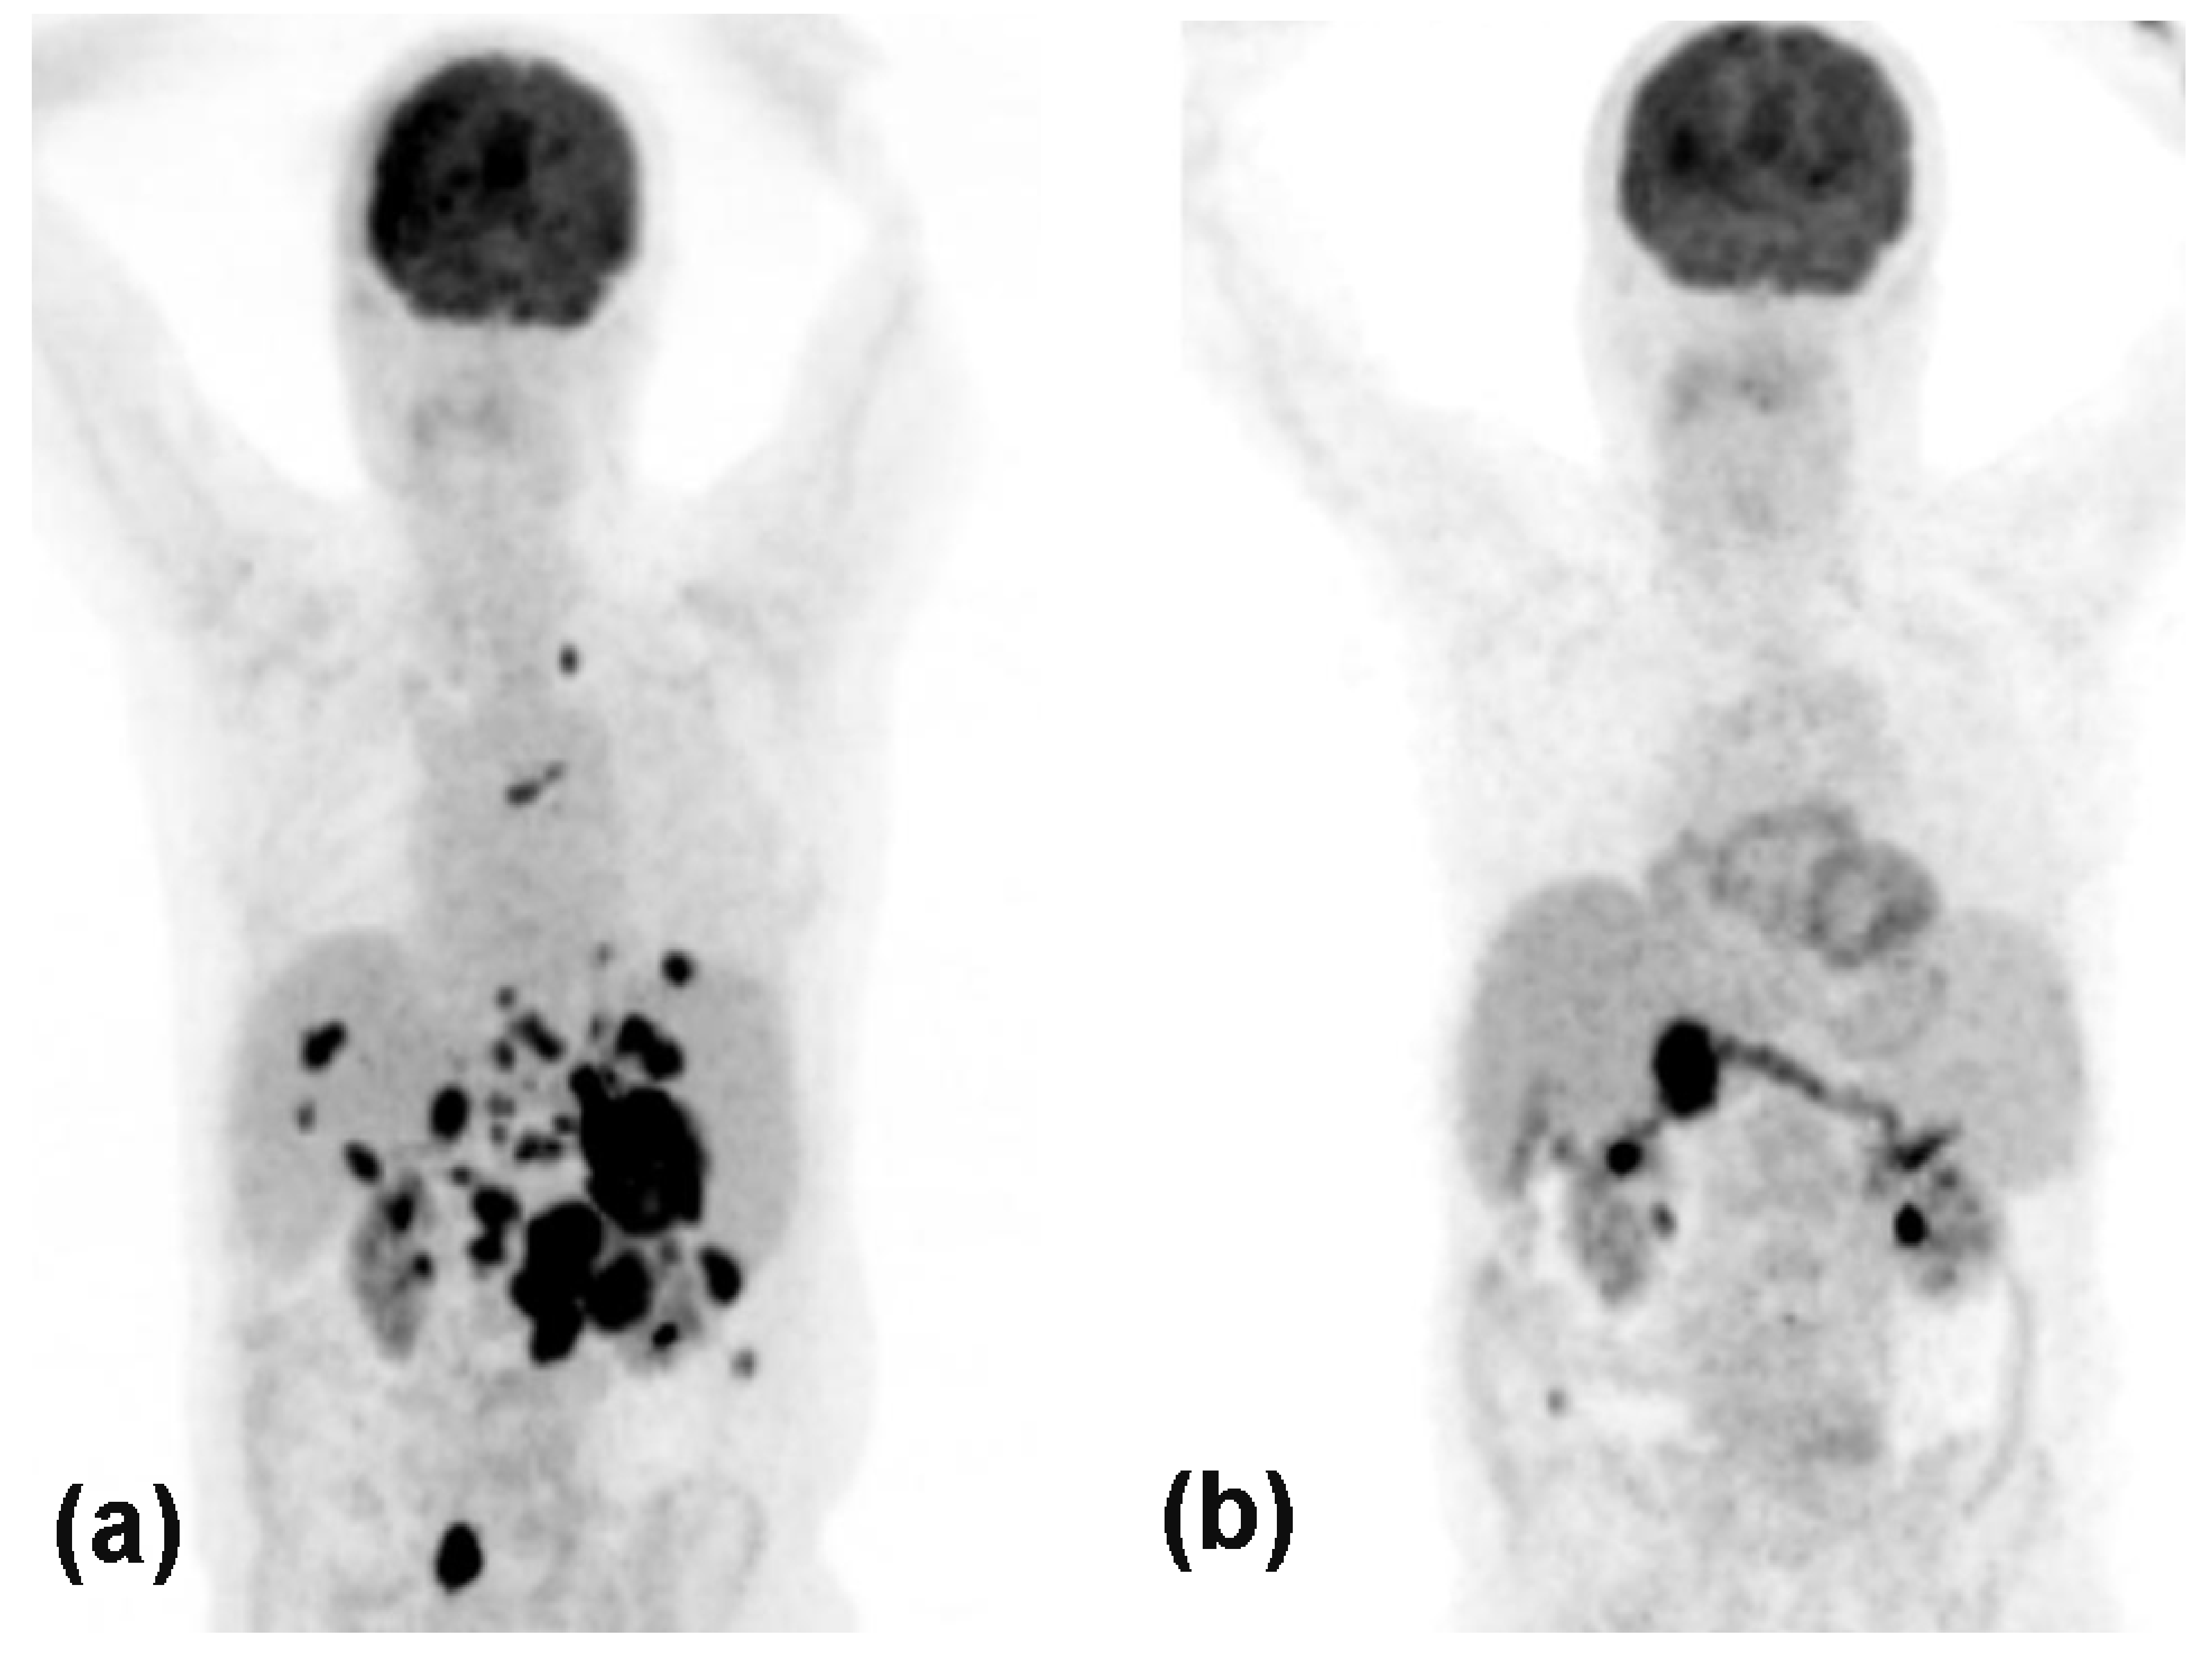

Figure 3.

PET-CT of an 80-year old male showing massive melanoma metastases in the entire abdomen (a), which almost completely resolved after two cycles of anti-PD-1 plus an-ti-CTLA-4 combination therapy (b).